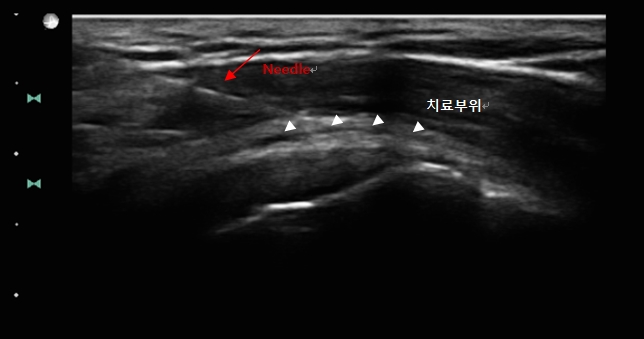

– 초음파를 이용한 프롤로치료요법